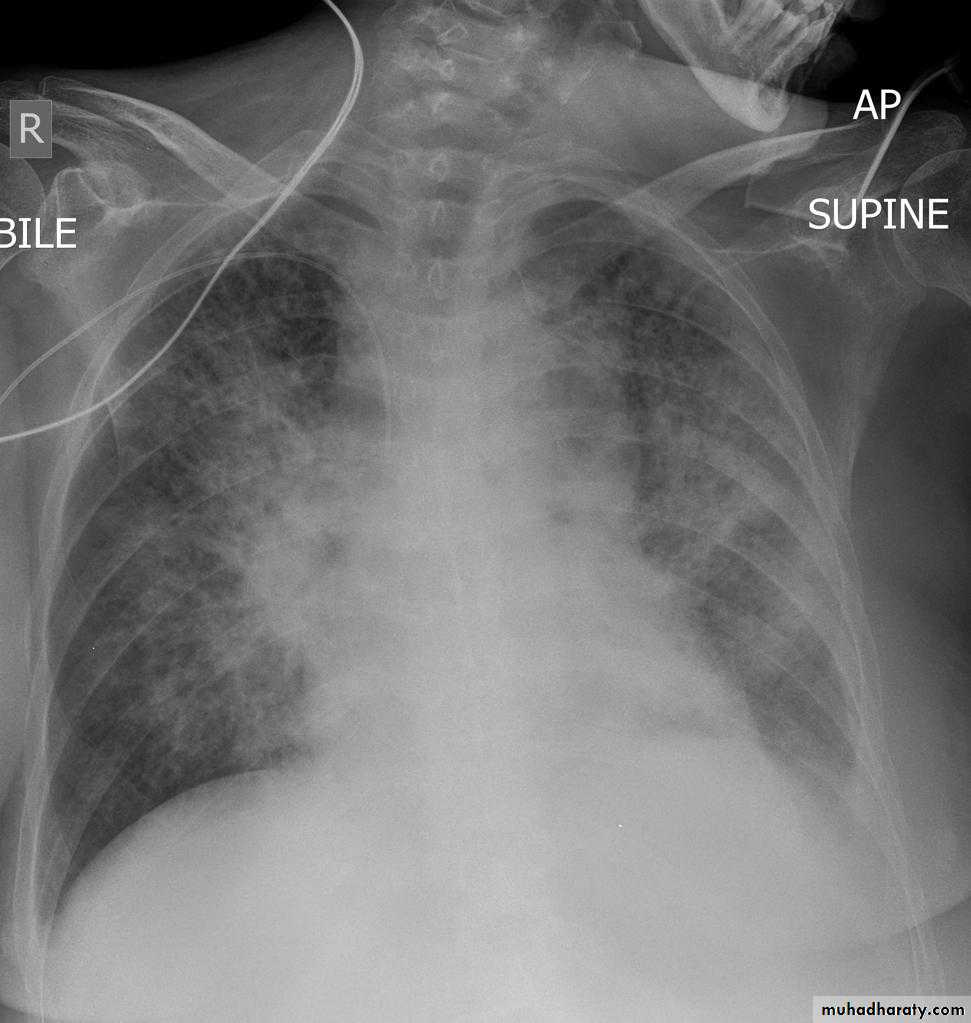

Interstitial pulmonary edema

Pulmonary edema ( alveolar pulmonary edema)

38.interstial pulmonary edema

39.pulmonary edema ( alveolar pulmonary edema )

40.batwing sign ( alveolar pulmonary edema )